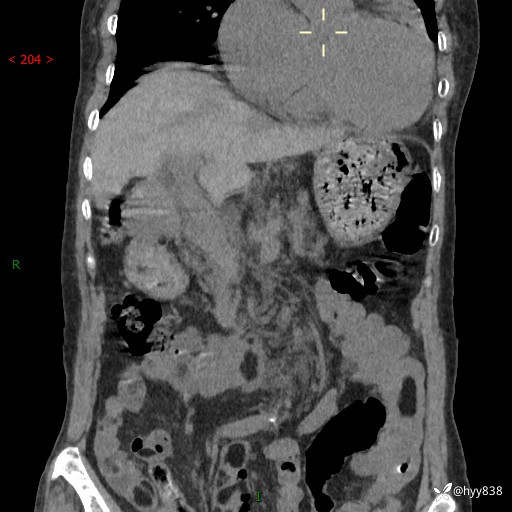

全腹部CT平扫